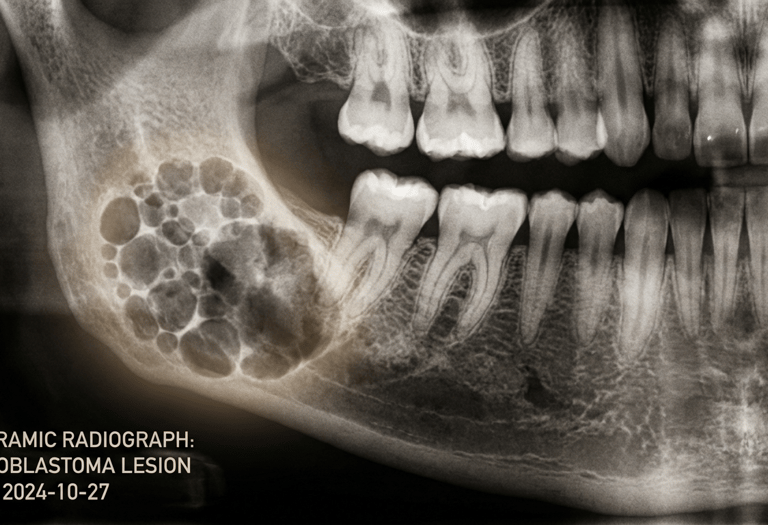

Jaw Cysts & Tumours

Expert surgical care for jaw cysts and tumours, with a strong emphasis on precision, safety, and comprehensive treatment planning.